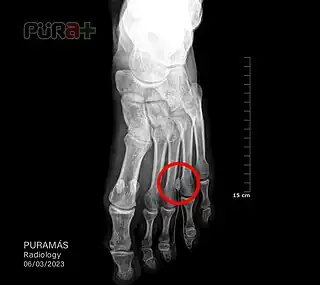

- Rayos X o Rx para descartar enfermedades óseas.